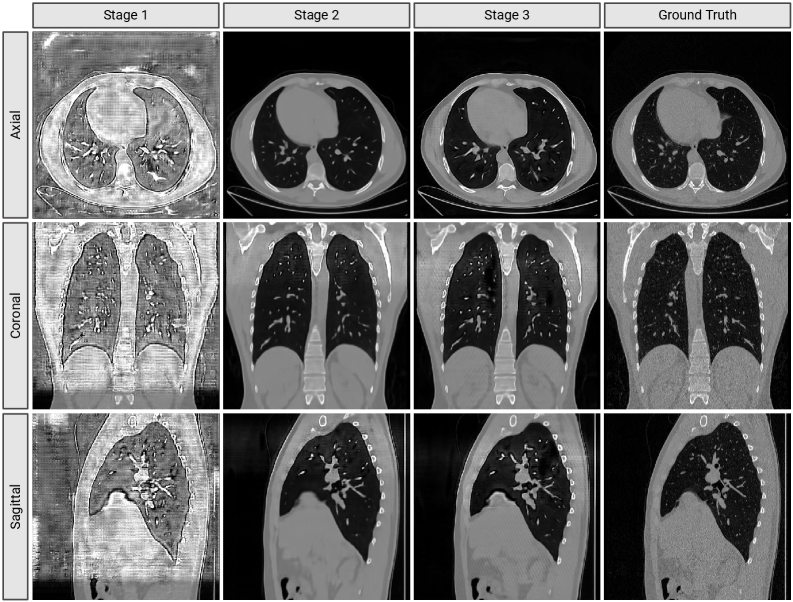

Table 1 reports reconstruction performance across training stages [44, 45]. Stage 1, trained on short subvolumes, captures local structure but fails at long-range consistency. Stage 2 introduces overlapping tiling, yielding the largest improvement: PSNR increases by over 14 dB, SSIM triples, and MSE drops an order of magnitude. Stage 3 refines inter-slice fidelity through decoder tuning, with modest but consistent gains. Figure 2 visualizes reconstruction quality (8×\times8×\times8 variant) across planes. Stage 1 outputs are blurry and lose structure beyond 9 slices. Stage 2 restores coherent anatomy across distant slices. Stage 3 sharpens fine boundaries such as fissures and vessels.

Refer to caption

Figure 2: Reconstruction results of our 8×\times8×\times8 model across axial, coronal, and sagittal planes after each training stage. Progressive improvements demonstrate the effectiveness of our three-stage strategy, with Stage 2 providing the largest gains in anatomical fidelity and inter-slice consistency.